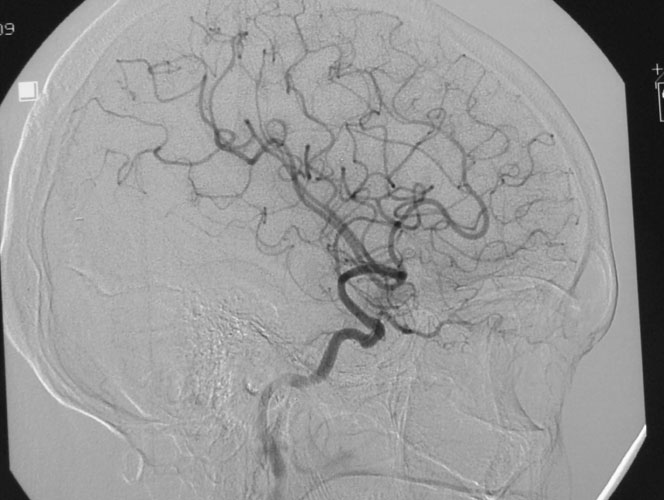

Aneurysms

Aneurysms are balloon-like outpouchings from an intracranial artery, that can rupture and present as subarachnoid hemorrhage. SAH constitutes an emergency, and if severe can be life threatening. Management is early diagnosis by brain imaging and cerebral angiography, followed by definitive treatment in the form of surgical clipping or endovascular coiling.